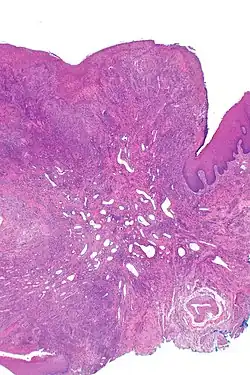

| Eosinophilic ulcer of the oral mucosa – H&E stain | |

Eosinophilic ulcer of the oral mucosa (also known as traumatic eosinophilic granuloma[1]) is a condition characterized by an ulcer with an indurated and elevated border.[2] The lesion might be tender, fast-growing and the patient often not be aware of any trauma in the area.